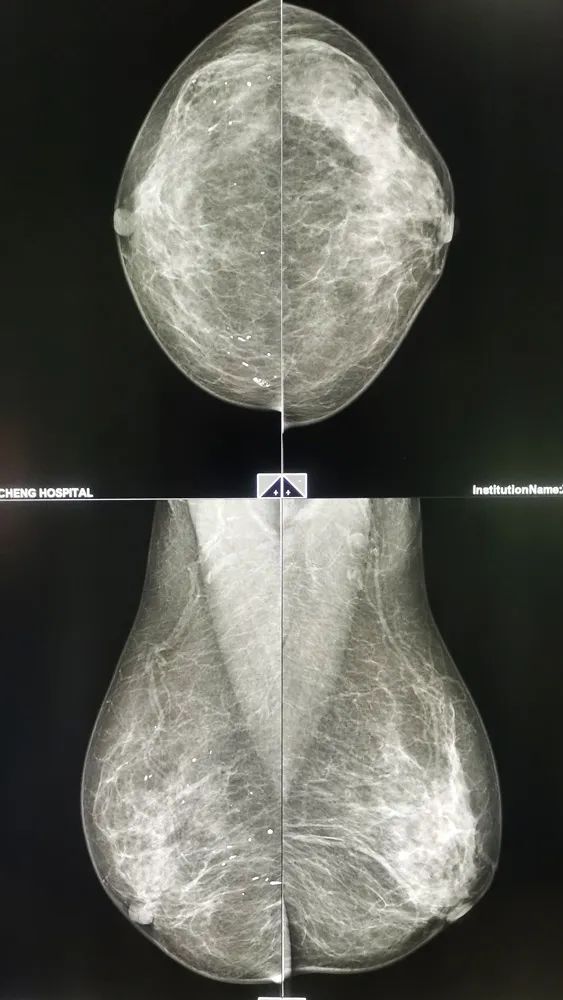

04、乳腺鉬靶篇

這份影像檢查必備的“省心”秘籍,相信一定會幫助到您!

乳腺鉬靶是乳腺疾病非;A的篩查檢查,能反映乳腺腺體內部的病變,以及優(yōu)勢是對于乳腺腺體內部鈣化非常的敏感,可以看得非常清楚,幫助發(fā)現(xiàn)早期乳腺癌。